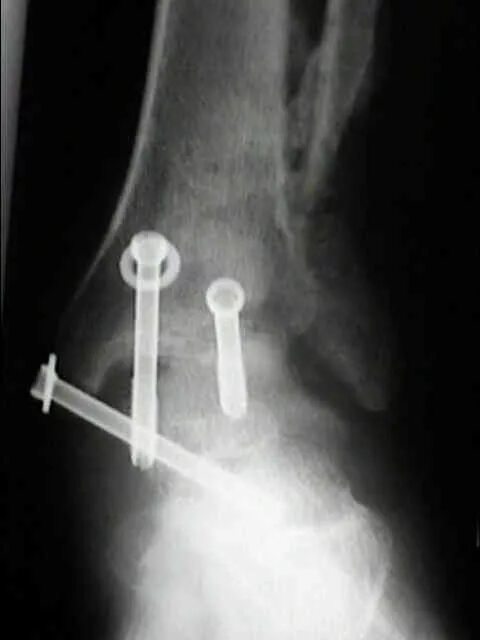

Артродез форум